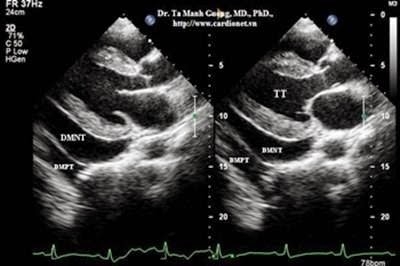

Đủ các xét nghiệm trước soi: phim chụp xquang phổi, CT scan ngực (nếu có), xét nghiệm công thức máu, đông máu cơ bản, chức năng hô hấp, AFB đờm, HIV, khí máu, điện tim đồ, siêu âm tim (nếu cần).